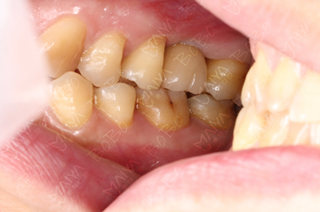

麦芽口腔中方院长游勤波和麦芽特邀专家孙海鹏博士指出许女士因蛀牙导致上牙左右两边第一磨牙缺失多年,已经影响到许女士的咀嚼功能,甚至影响食欲和破坏肠胃健康,过早牙缺失,会导致一系列的身体危害而不自知。出于对身体健康方面考虑,决定为许女士采用种植牙修复并成功种下德系品牌种植体。

植牙模拟判断咬合程度